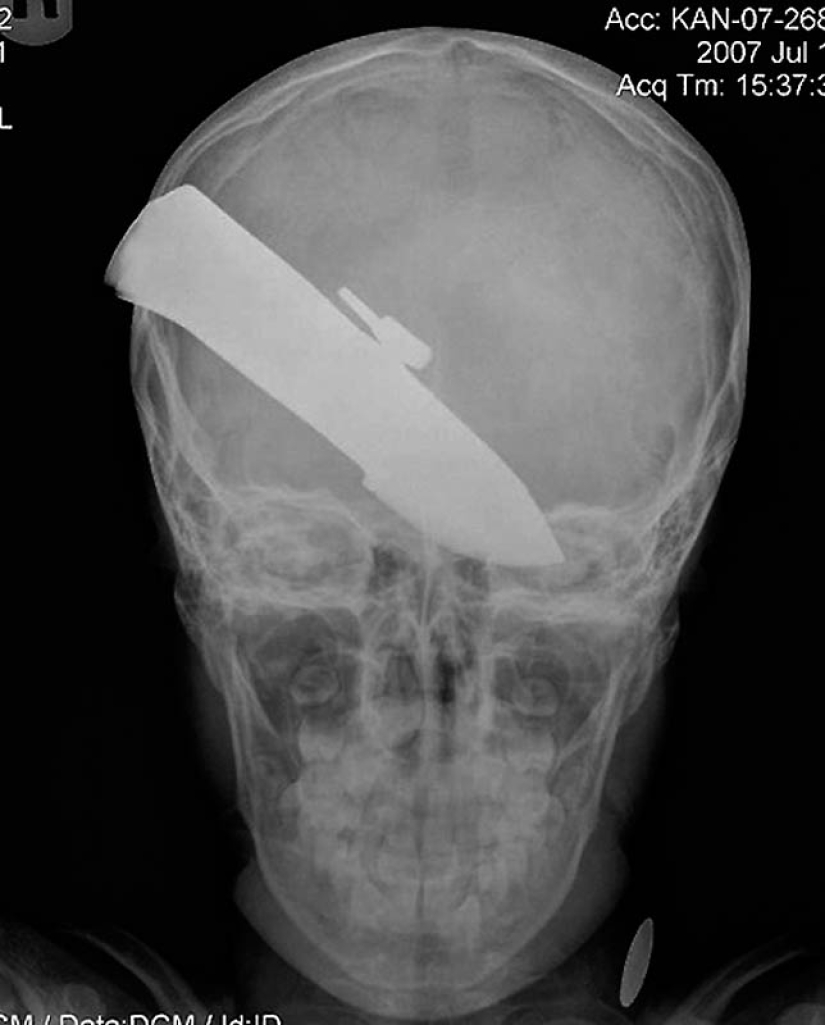

15. Un cuchillo en la cabeza de un niño de 10 años. El chico sobrevivió.

18. un cuchillo de 12 centímetros en el cráneo de un adolescente.